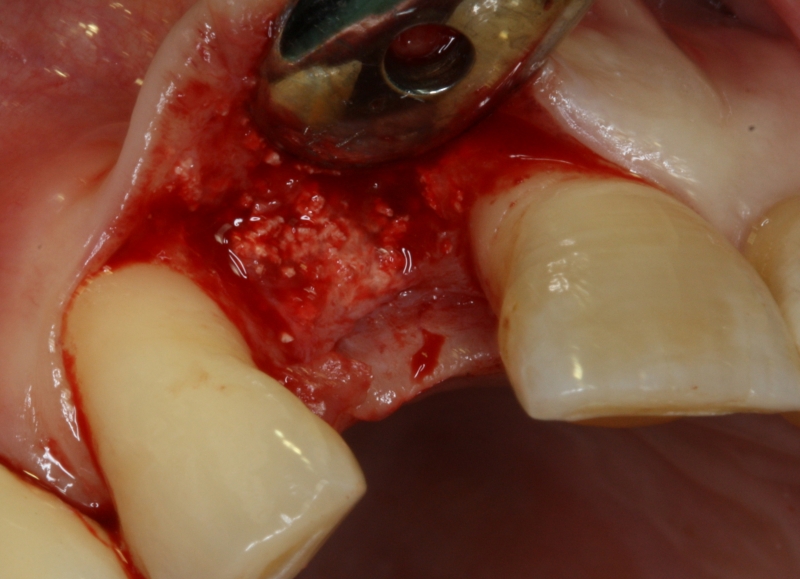

08/20 - Surgical presentation of the alveolar ridgeGBR with maxresorb® & Jason® membrane - Prof. Dr. Dr. D. Rothamel